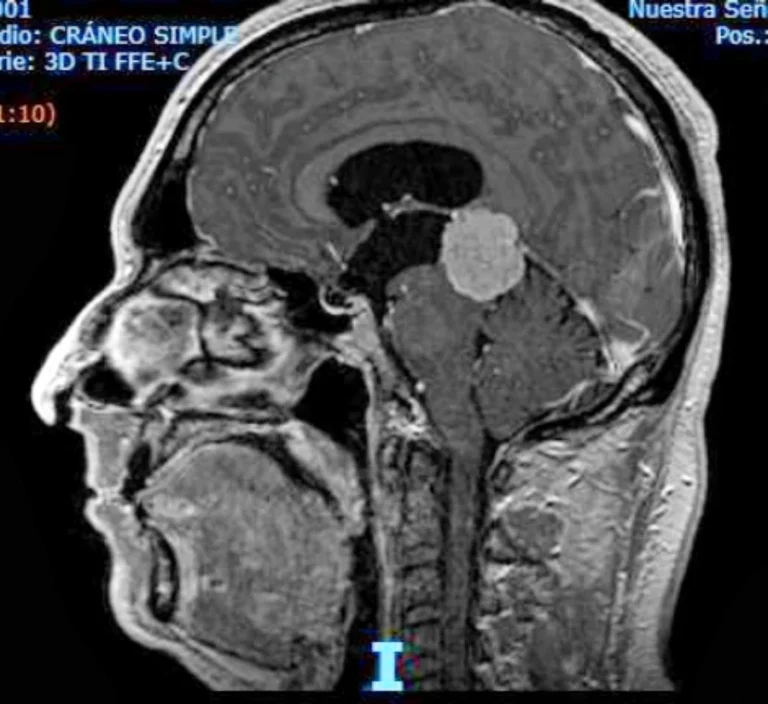

Hidrocefalia arreabsortiva en el adulto

Video-charla del Dr. García de Sola sobre la Hidrocefalia arreabsortiva Hidrocefalia arreabsortiva en el adulto La hidrocefalia arreabsortiva del adulto, también llamada hidrocefalia crónica o de presión normal, es una patología neurológica que surge por alteraciones en la dinámica del líquido cefalorraquídeo (LCR). Para comprenderla, primero se explica la fisiología del LCR: este líquido transparente …